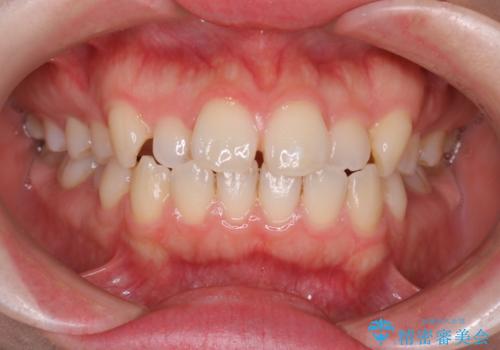

- 前歯の凸凹と口元の突出感を主訴に来院されました。

臼歯関係が上顎前突傾向のため、上の小臼歯を抜歯してワイヤー矯正を行なっております。

下顎の叢生はIPRを行なって配列しています。